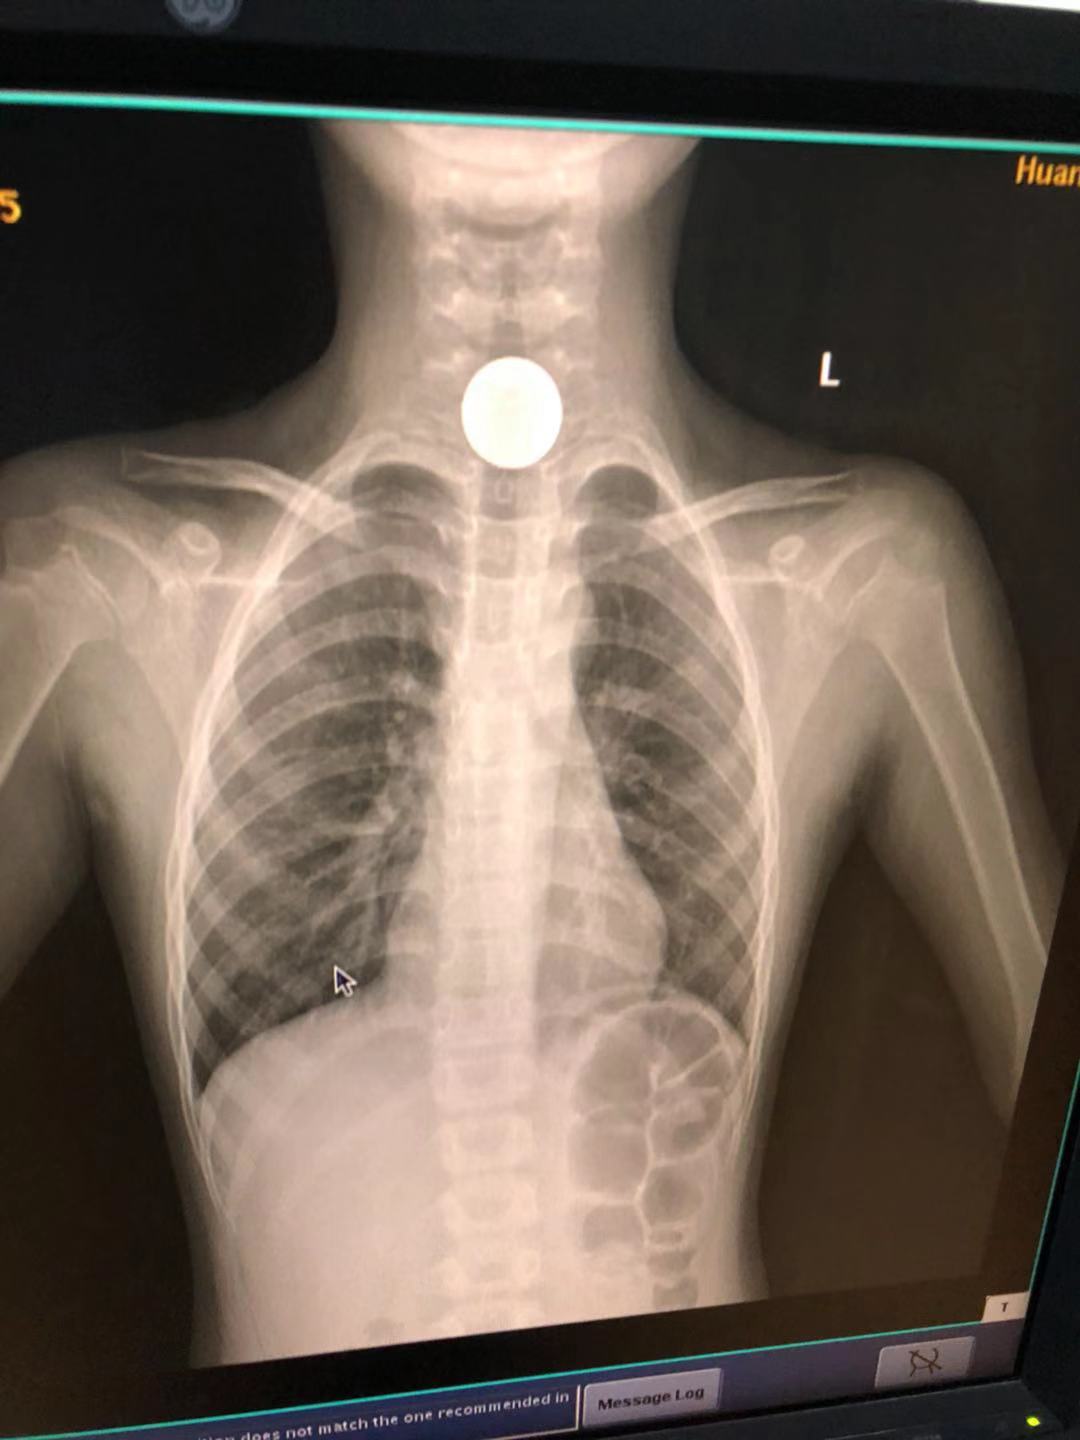

約17:00時(shí),患兒家屬將孩子送到北京愛康醫(yī)療集團(tuán)旗下黃石愛康醫(yī)院,門診檢查顯示咽喉部粘膜淡紅,雙側(cè)扁桃體無明顯腫大,口水較多,間接喉鏡下會(huì)厭光滑,抬舉可;雙側(cè)梨窩有少量粘白痰液,雙側(cè)聲帶及聲門窺視不清。建議拍片子,門診胸片提示考慮食道頸段異物。

門診坐診醫(yī)師柯國(guó)華主任結(jié)合病史及胸片提示明確食道上段金屬異物,異物卡在食道第一狹窄環(huán),需要緊急入院進(jìn)行硬質(zhì)食道鏡下取異物,馬上手術(shù)。

該女童術(shù)前胸片圖